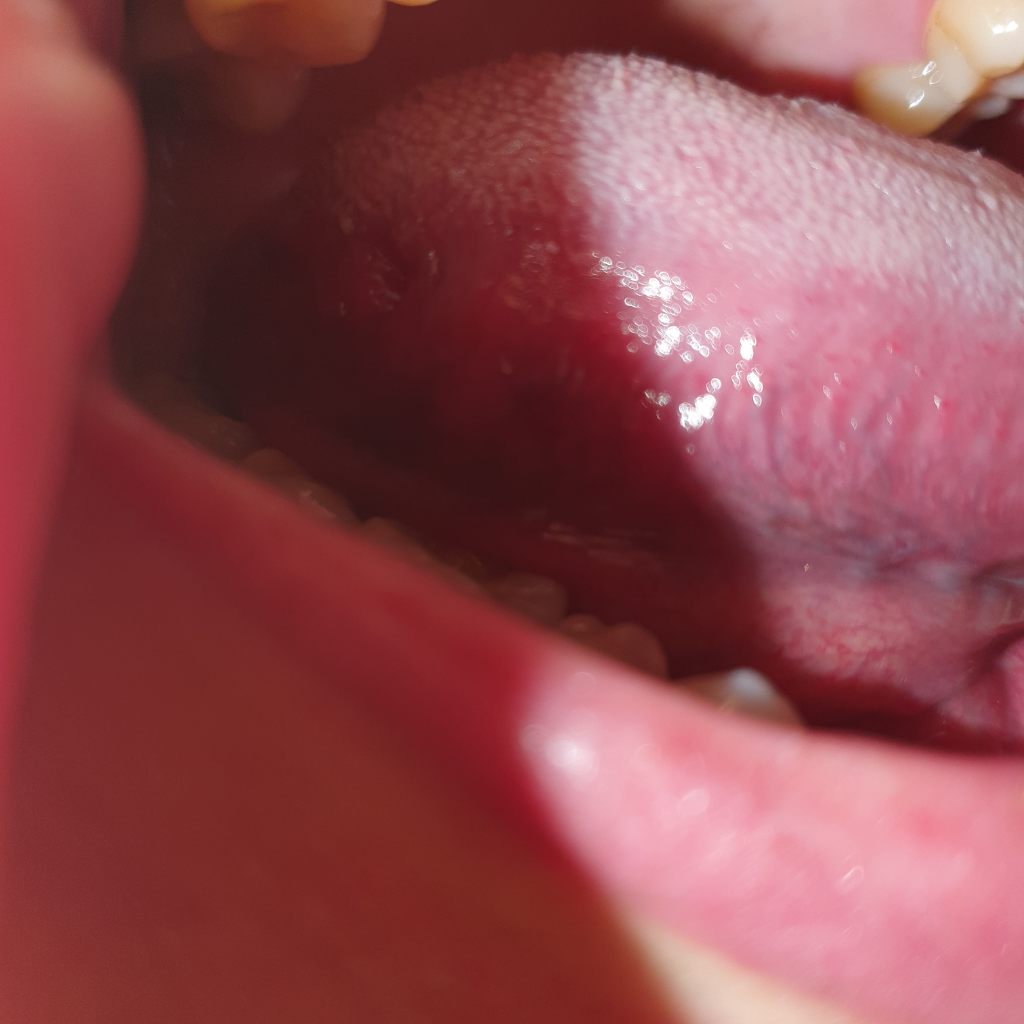

혀 측면 안쪽 정상인가요? 사진

혓바늘 생긴거같아서 확인하는데 ㅠㅠ

혀안쪽에 이런게잇더라구요

검색해도 정상인지모르겠는데...

문제있는건가요?..

(오른쪽혀측면) 아래네장

혀의 경우는 현재 통증 등이 없는 상황이라면 정상소견으로 볼 수 있겠습니다.